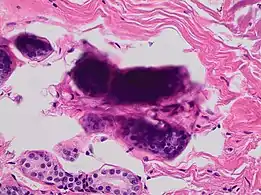

In microscopy, an artifact is an apparent structural detail that is caused by the processing of the specimen and is thus not a legitimate feature of the specimen. In light microscopy, artifacts may be produced by air bubbles trapped under the slide's cover slip.[1]

A crush artifact is an artificial elongation and distortion seen in histopathology and cytopathology studies, presumably because of iatrogenic compression of tissues. Distortion can be caused by the slightest compression of tissue and can provide difficulties in diagnosis.[2][3] It may cause chromatin to be squeezed out of nuclei.[4] Inflammatory and tumor cells are most susceptible to crush artifacts.[4]

Crush artifact from compression by forceps on the tissue sample